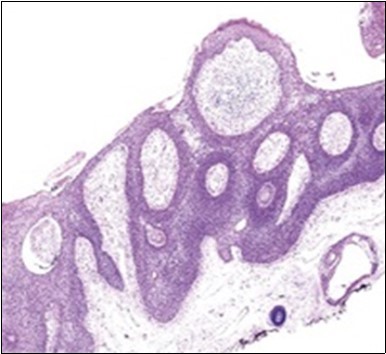

Granular arrangement of malignant cells and intercellular bridges are conspicuous with the demonstration of nuclear atypia, pleomorphism, prominent mitosis and tumour necrosis. A peripheral palisade is discernible within the cellular aggregates. Mitotic figures are common and can be quantified as up to 12 mitosis/ high power field. Tumour differentiation can prominently be of the ductal category with the demonstration of intra-cytoplasmic lumina. Comedo type tumour necrosis is evident along with foci of squamous differentiation The neoplasm is reactive to periodic acid Schiff ‘s (PAS) stain. (Figure 1, Figure 2, Figure 3, Figure 4, Figure 5, Figure 6, Figure 7, Figure 8, Figure 9, Figure 10, Figure 11, Figure 12, Figure 13.

Figure 2.Epidermal projections lined with atypical and malignant epithelial cells in eccrine porocarcinoma (14).

The neoplasm is composed of lobules of aberrant epithelial cells configured in cords with incrimination of the dermis and epidermis.. Malignant cells congregate within the epidermis or infiltrate the dermis, especially in the primary tumour. Tumour cells within tumour aggregates display a well demarcated cellular outline and appear distinct from encompassing squamous cells. Numerous tumour cell clusters demonstrate a cystic lumen. Prominent epidermal acanthosis is discerned on account of tumour cell proliferation 6, 7.

Eccrine porocarcinoma is an infiltrative, high grade tumour which is contiguous with superimposed epidermis, depicts a partially lobular architecture and a diameter usually exceeding > 90 millimetres. An endophytic pattern of tumour evolution is elucidated with invasion of deep reticular dermis and subcutaneous tissue 5, 6.